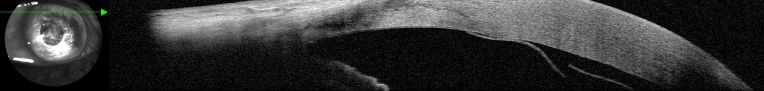

In cases where severe corneal edema is present, other diagnostic tests can aid the diagnosis. The most used and accurate exam for the diagnosis of DMDs is the anterior segment optical coherence tomography (AS-OCT). AS-OCT is a quick, non-contact modality that can determine the exact location, configuration, and extent of the DMD, not only confirming the diagnosis but also guiding the treatment method and outcomes[7].

The diagnosis of DMD is mostly clinical, based on history and slit lamp examination, especially if the cornea is clear. However, if there is significant corneal edema, imaging tools such as anterior segment optical coherence tomography (AS-OCT) are fundamental for the diagnosis.